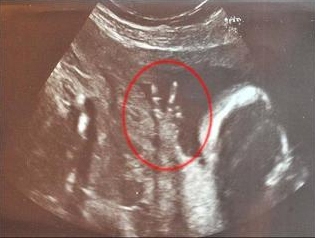

中新网7月10日电 据台湾东森新闻报道,即将为人母的英国女子卡罗琳巴恩斯已怀孕23周。最近她去照超声波,结果发现肚子里的孩子竟然比出结结实实的V字型胜利手势。

目前35岁,在电视台担任分区经理的卡罗琳说:“医院里的护士笑到不行。在照超声波的整个过程中,他的手势都是这个样子。”